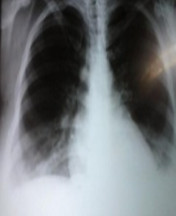

Volver a los detalles del artículo Preeclampsia grave y mola hidatiforme embrionada con feto vivo